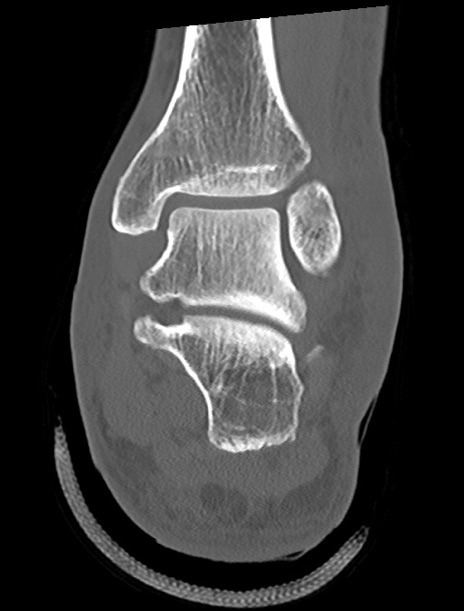

左足関節CT

矢状断像